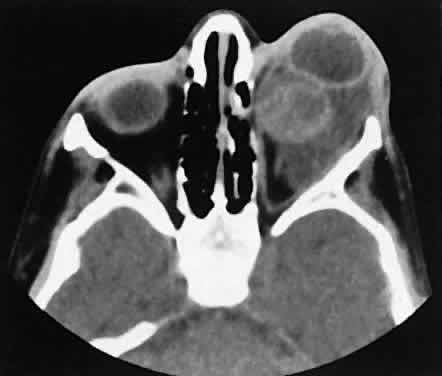

Dermoid cysts are located most frequently in the superior temporal quadrant of the orbit. They may be located anywhere within the orbital confines. Lesions in the lacrimal fossa or along the posterior lateral wall may communicate intracranially or into the temporalis fossa. Radiographically, the cysts are well-delineated and have lucent interiors with CT attenuation densities in the fat range (Fig. 19). Calcification along the rim of the cyst may be present. The bony changes have irregular, notched borders rather than the moth-eaten appearance associated with malignancy. The range of CT appearances can be quite wide.67

Fig. 19. Axial (A) and coronal (B) scans of a dermoid cyst. Note the low attenuation (lower than retrobulbar fat) within the well-demarcated cyst located in the right lacrimal gland fossa.